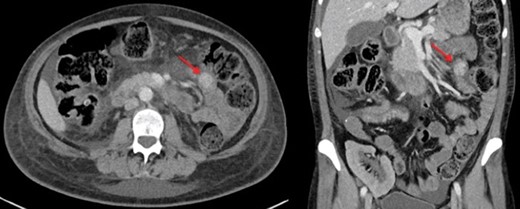

A renal biopsy was performed and showed atypical glomerulopathy with immune complexes. An autoimmune panel was negative. Investigations were performed to assess the presence of an inflammatory or infectious process. An abdominopelvic computed tomography (CT) scan revealed a hyperdense mass in the small bowel (Fig. 1). CT enterography further showed a 2 cm homogeneous jejunal lesion with no extraluminal extension (Fig. 2). Positron emission tomography scan displayed no hypermetabolism in the small bowel or in the renal allograft. Differential diagnosis included gastrointestinal stromal tumor and leiomyoma, but due to the transplant immunosuppression and the Epstein-Barr viral load of 16 596 copy/mL, a post-transplant lymphoproliferative disease (PTLD) was highly suspected.